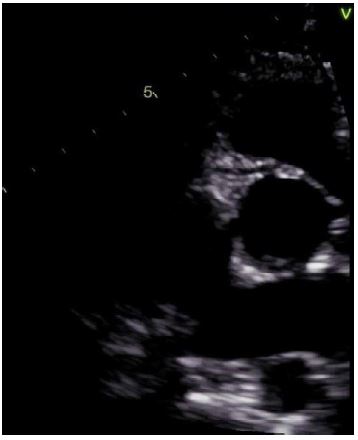

A 17-year-old male presented to the cardiology clinic for evaluation of a 3-year history of burning intermittent chest pain associated with exertion. He declined shortness of breath or loss of consciousness. His vital signs were unremarkable except for a blood pressure of 135/90. His family history was significant for hypertension. His physical exam and electrocardiogram (ECG) were normal. His 2D Echo suggested normal coronary origins (Figure 1), but color Doppler of the right coronary artery (RCA) was abnormal (Figure 2). An exercise stress revealed significant ST changes with ST depression and T wave inversion in inferior and lateral leads during maximum exercise and during recovery. CTA of the coronaries demonstrated that the RCA arose from the left wall of the ascending aorta, superior to the origin of the LMCA, with a 7mm intramural course and narrowed caliber (Figures 3 and 4). The RCA gave rise to the posterior descending coronary artery. After consideration of risks and benefits, he underwent unroofing of the RCA intramural course and tolerated the surgery without complications. He currently plays basketball with no symptoms.

Figure 1: 2D echocardiogram clip suggesting normal origin of the RCA from the right coronary sinus.

Figure 2: Color Doppler Echocardiogram demonstrating abnormal flow that was thought to be in the RCA.